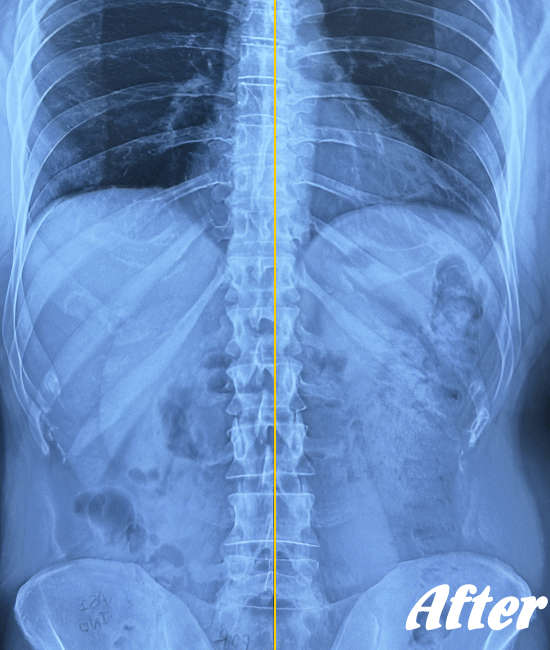

病院では、側弯の程度はレントゲンによる画像検査で弯曲の程度を調べます。

Cobb角(コブ角)とは、背骨の曲がり具合の角度を表す用語ですが、コブ角が10~25度程度なら経過観察。コブ角が25°~40°程度ならコルセットなどの装具を装着する療法、コブ角が40°~50°以上であれば手術…といった目安になります。

軽度の突発性側弯症であれば、運動療法で経過観察、進行性であれば専用のコルセットなどの装具着用。悪化する場合は、外科的手術で器具を埋め込み脊柱を固定することが検討されます。

先天性や弯曲角度が大きい突発性側弯症は適応外になりますが、普段の姿勢の悪さに起因する機能性側弯症や初~中期の突発性側弯症であれば、施術対象になります。

ただし、弯曲が20°以上になると改善が難しくなってきます。また、脊柱(背骨)が側屈しているだけなら良いのですが、椎骨が回旋してしまっている場合の改善は、肋骨の変形もともなうため改善が難しくなります。

したがって、側弯症は腰周りの筋肉を緩め腰の骨をまっすぐにしていくことを中心に、施術を行っていきます。腰がまっすぐになれば、身体はバランスを保とうと勝手に上部もまっすぐにしてくれます。